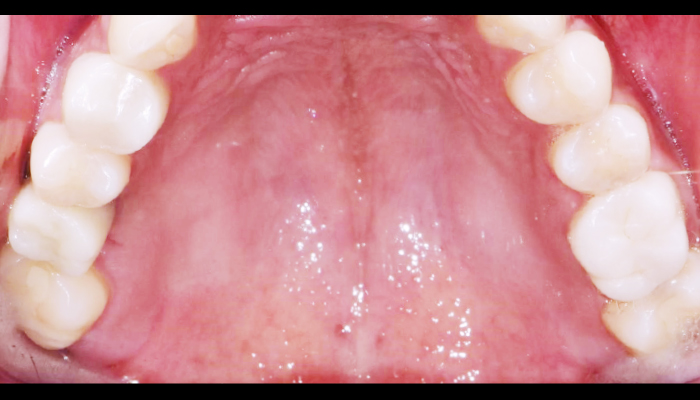

Before

로그인 후 이용해주세요

After

매복 사랑니 발치

이OO님 전후사진 / 치료 기간 : 30분 / 당일 사랑니 발치

Before

로그인 후 이용해주세요

After

매복 사랑니 발치

이OO님 전후사진 / 치료 기간 : 30분 / 당일 사랑니 발치